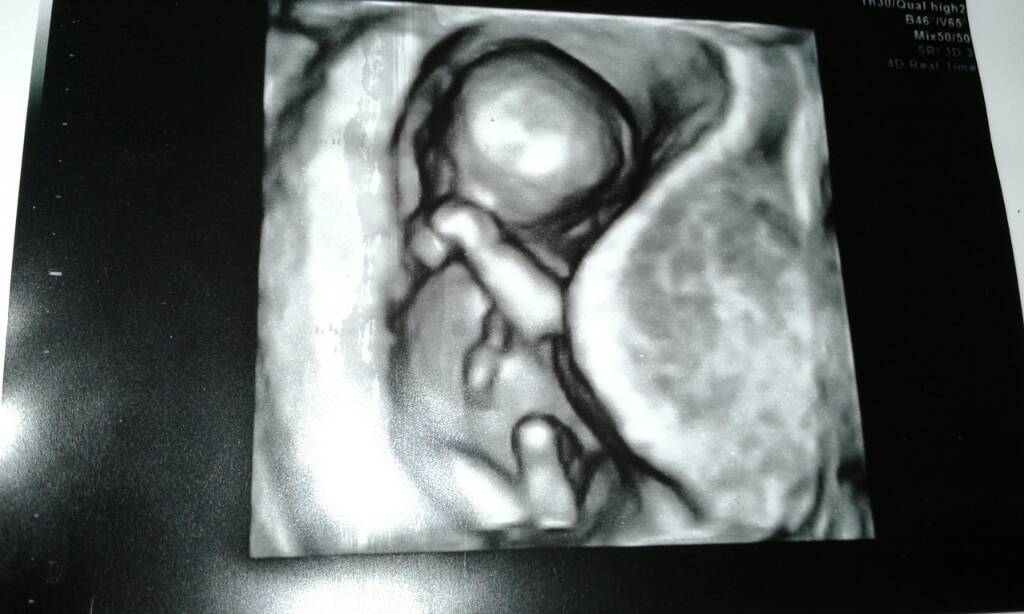

To moja dzidzia :)

Millo Jak dzidzia była mniejsza to miejsca sporo było, na usg też się wydaje ze luzik ma.Zdjęcie Wam wstawiłam pionowo,a faktycznie to dzidzia leży na pleckach i tak jakby bokiem. Trzeba by sobie fotkę położyć w drugą stronę hehe:) no i na tych 3d/4d to robią takie dziwne ujęcia ze starają się jak najbardziej od przodu zrobić fotkę.